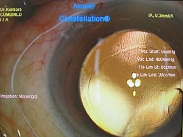

黄斑円孔の手術に関しては、?で記載しましたが、簡単におさらいすると、目の中に器械をいれて、内境界膜という網膜の表層の膜を剥離し、網膜を柔らかくします。その後、目の中に空気を入れてうつ伏せをすることで、円孔の周囲の網膜を浮力で引き寄せて、穴を閉じる。という方法です。

?手術の効果で、青や緑の網膜を中心部に引き寄せます。

?青の部分の網膜が、視野の中心部の視界を担うようになります。